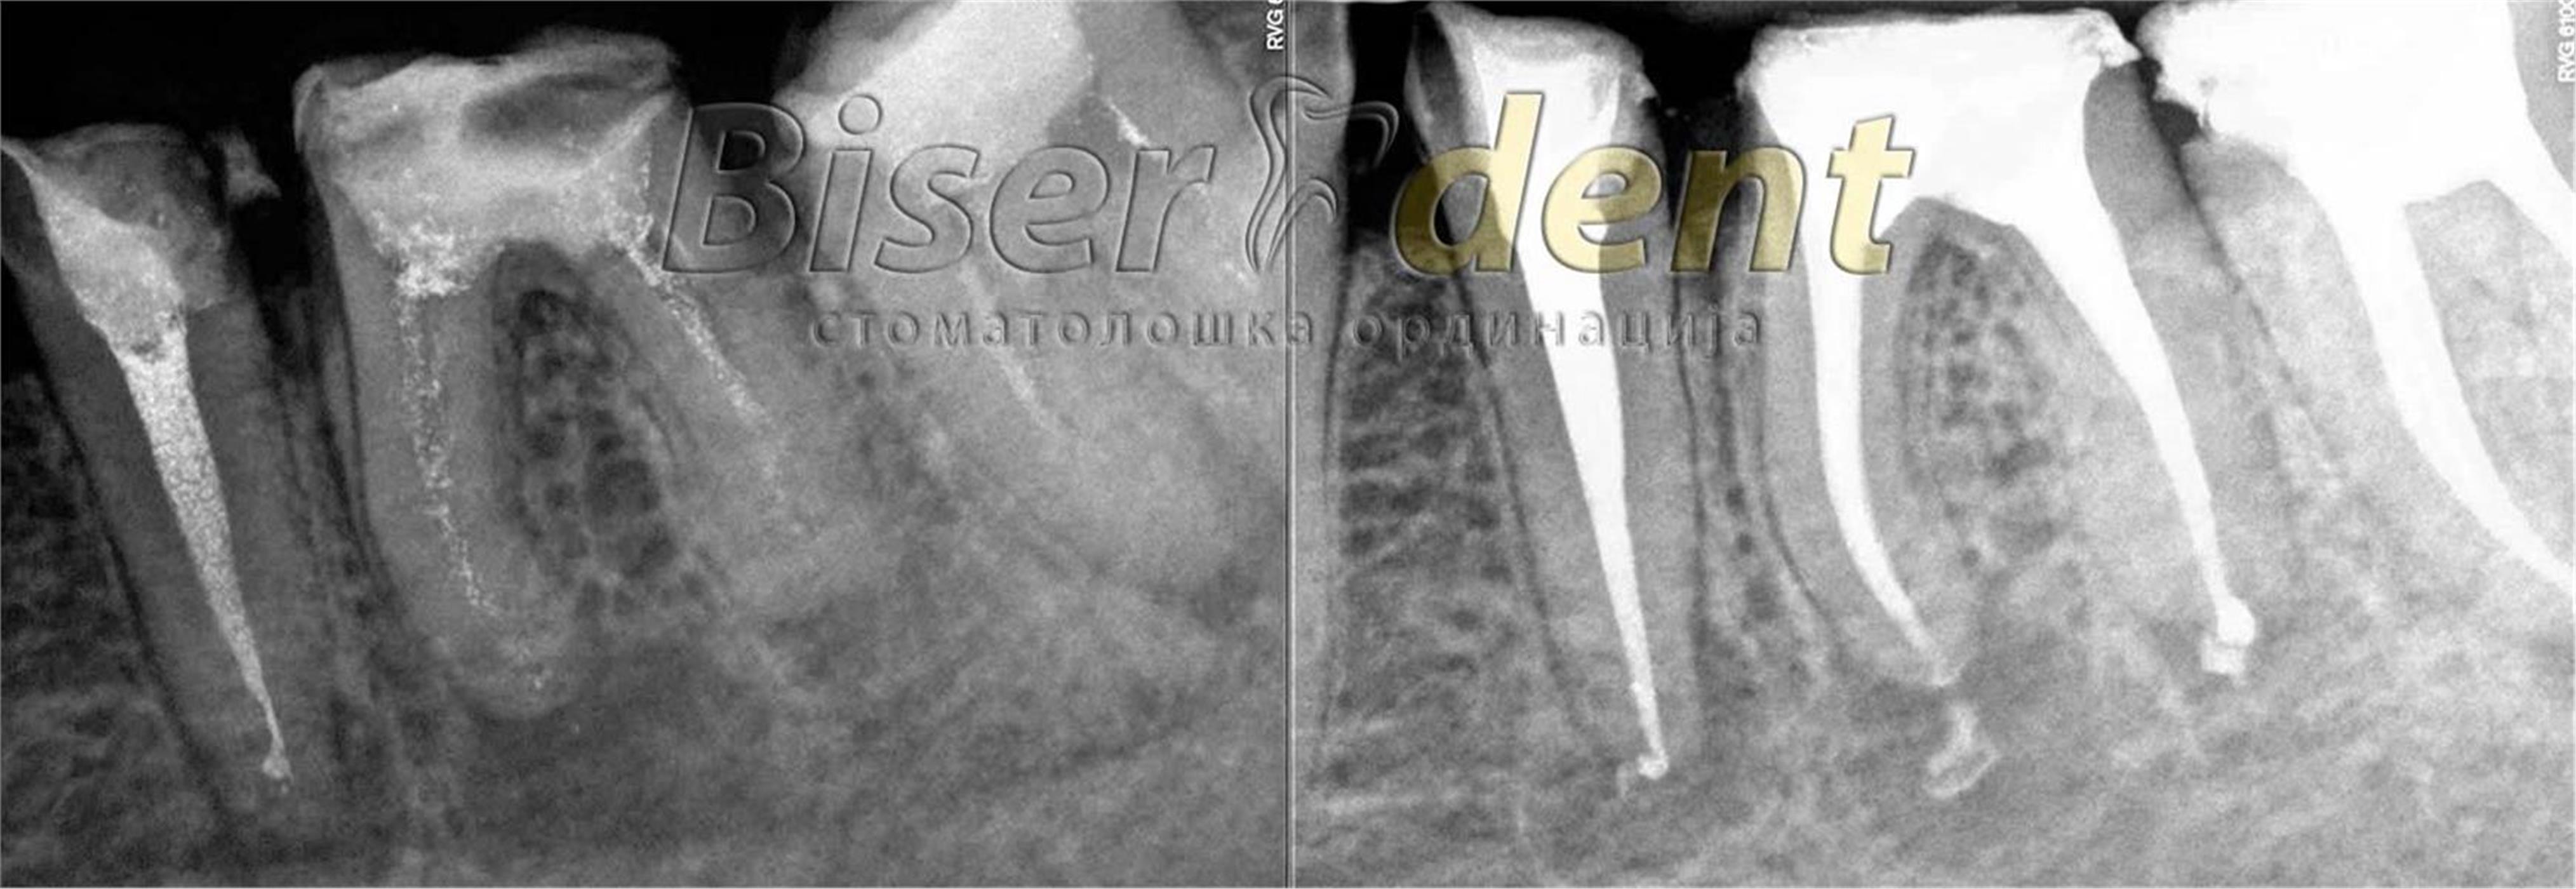

Современата ендодонција е целосно застапена во нашата ординација. Тоа вклучува примена на апекс локатор (за прецизно одредување на должината на коренските канали), системи за машинска обработка на истите (Protaper, Endo eze), системи за иригација (испирање) и дезинфекција на каналите, ласер за комплетна стерилизација, високо квалитено полнење и секако потврда на спроведениот ендодонтски третман со рентген снимка.

РЕВИЗИЈА